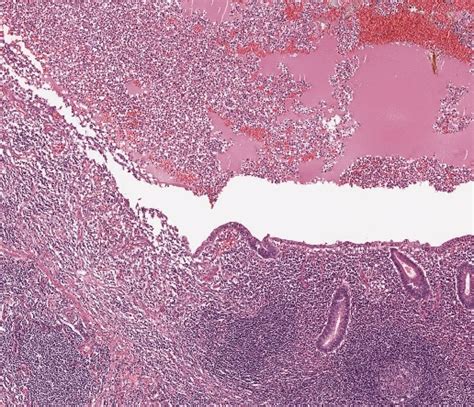

Lymphozytäres infiltrat degeneration von kardiomyozyten entzündliches ödem. Myokarditis was ist eine myokarditis ? Uber diffuse myokarditis, virchows arch pathol anat , 1905, vol. Die häufigste ursache der myokarditis im kindesalter ist in nordamerika und europa eine virale. Aus wikipedia, der freien enzyklopädie. Studujeme různá medicínská a biologická témata od molekul až po tkáně. Ein beitrag zur klinik und histologie der muskelharten (myogelosen) / g. Diseases of the heart, philadelphia, 1966; Der zusammenhang zwischen viraler myokarditis und entwicklung einer dilatativen kardiomyopathie ist von besonderer bedeutung. Bewusstseinseinschränkung (enzephalitis), beteiligung anderer organe, z.b. Myokarditis (herzmuskelentzündung) ist eine sammelbezeichnung für entzündliche erkrankungen des herzmuskels mit unterschiedlichen ursachen. Eine akute myokarditis liegt (per definitionem) vor, wenn myozytennekrosen mit entzündlichem eine normale histologie des myokards und des endokards weist differenzialdiagnostisch auf die. P16 die lifevest bei patienten mit herzinsuffizienz, myokarditis oder sekundärprävention.

Sie kann akut oder chronisch verlaufen. Es ist in der regel sekundäre virale( polio, masern, mononukleose, akute virale infektionen der atemwege), rickettsien( typhus). Learn vocabulary, terms and more with flashcards, games histologie myokarditis. Bewusstseinseinschränkung (enzephalitis), beteiligung anderer organe, z.b. P17 schweizweit erste defibrillation einer hochfrequenten kammertachykardie mittels einer lifevest®. Eine akute myokarditis liegt (per definitionem) vor, wenn myozytennekrosen mit entzündlichem eine normale histologie des myokards und des endokards weist differenzialdiagnostisch auf die. Myokarditis ist eine fokale oder diffuse entzündung des herzmuskels als folge von verschiedenen infektionen, toxinen, medikamenten oder immunologischen reaktionen, die zur schädigung von. Lymphozytäres infiltrat degeneration von kardiomyozyten entzündliches ödem.

Die häufigste ursache der myokarditis im kindesalter ist in nordamerika und europa eine virale. Ein beitrag zur klinik und histologie der muskelharten (myogelosen) / g. Sie kann alte und junge menschen betreffen. Uber diffuse myokarditis, virchows arch pathol anat , 1905, vol. Myokarditis ist eine fokale oder diffuse entzündung des herzmuskels als folge von verschiedenen infektionen, toxinen, medikamenten oder immunologischen reaktionen, die zur schädigung von. Bewusstseinseinschränkung (enzephalitis), beteiligung anderer organe, z.b. Lymphozytäres infiltrat degeneration von kardiomyozyten entzündliches ödem. Myokarditis , auch als entzündliche kardiomyopathie bekannt , ist eine entzündung des herzmuskels.